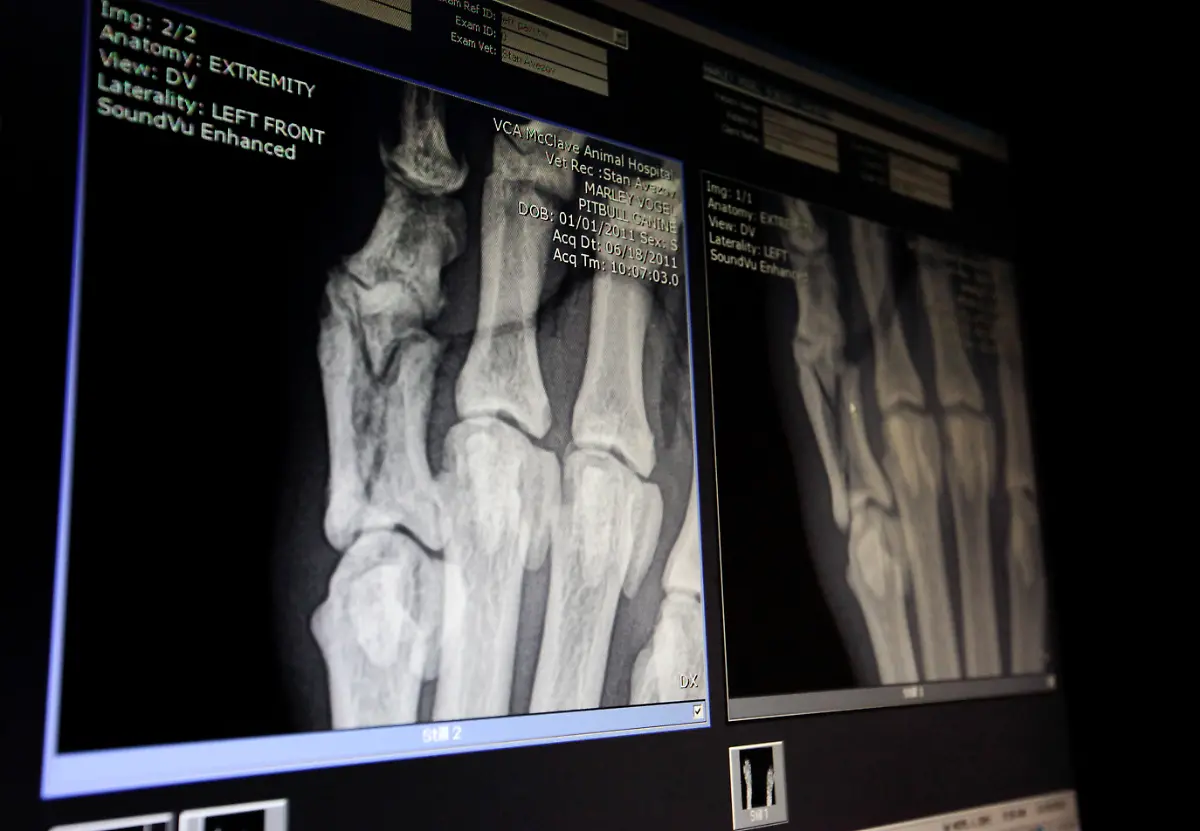

Socken, Kieselsteine, Außerirdische - Röntgenbilder von Mägen US-amerikanischer Haustiere zeigen die skurrilsten Gegenstände. Eine Zeitschrift zeichnet jedes Jahr die außergewöhnlichsten Aufnahmen aus.